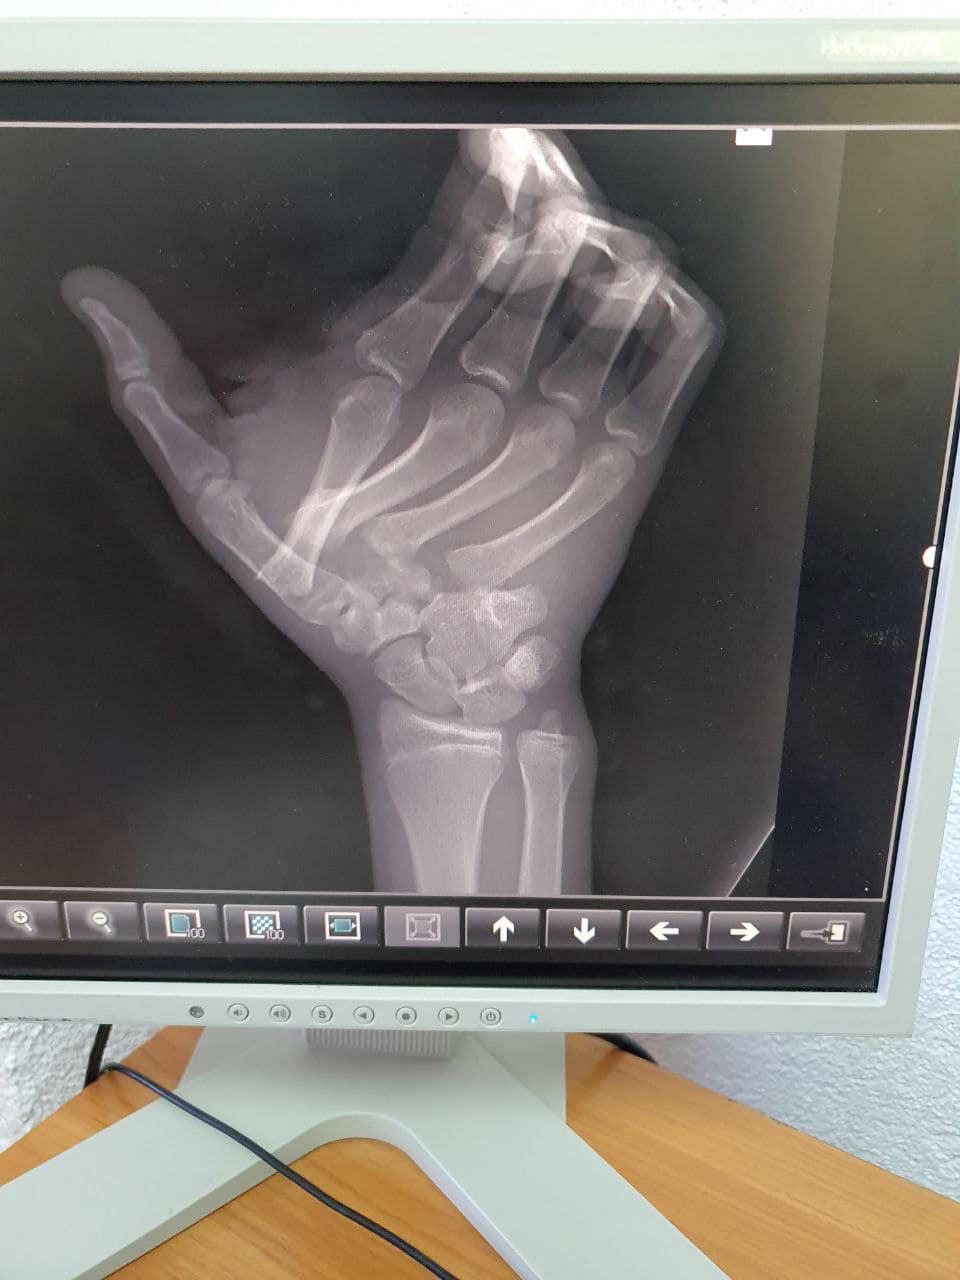

Сообщается, что парень получил переломы и вывихи нескольких костей запястья и переломы с открытыми рвано-резанными ранами в области первого и второго пальцев.

Отмечается, что кости пальцев травматологи зафиксировали четырьмя спицами Киршнера, которые пациент носит уже около месяца.